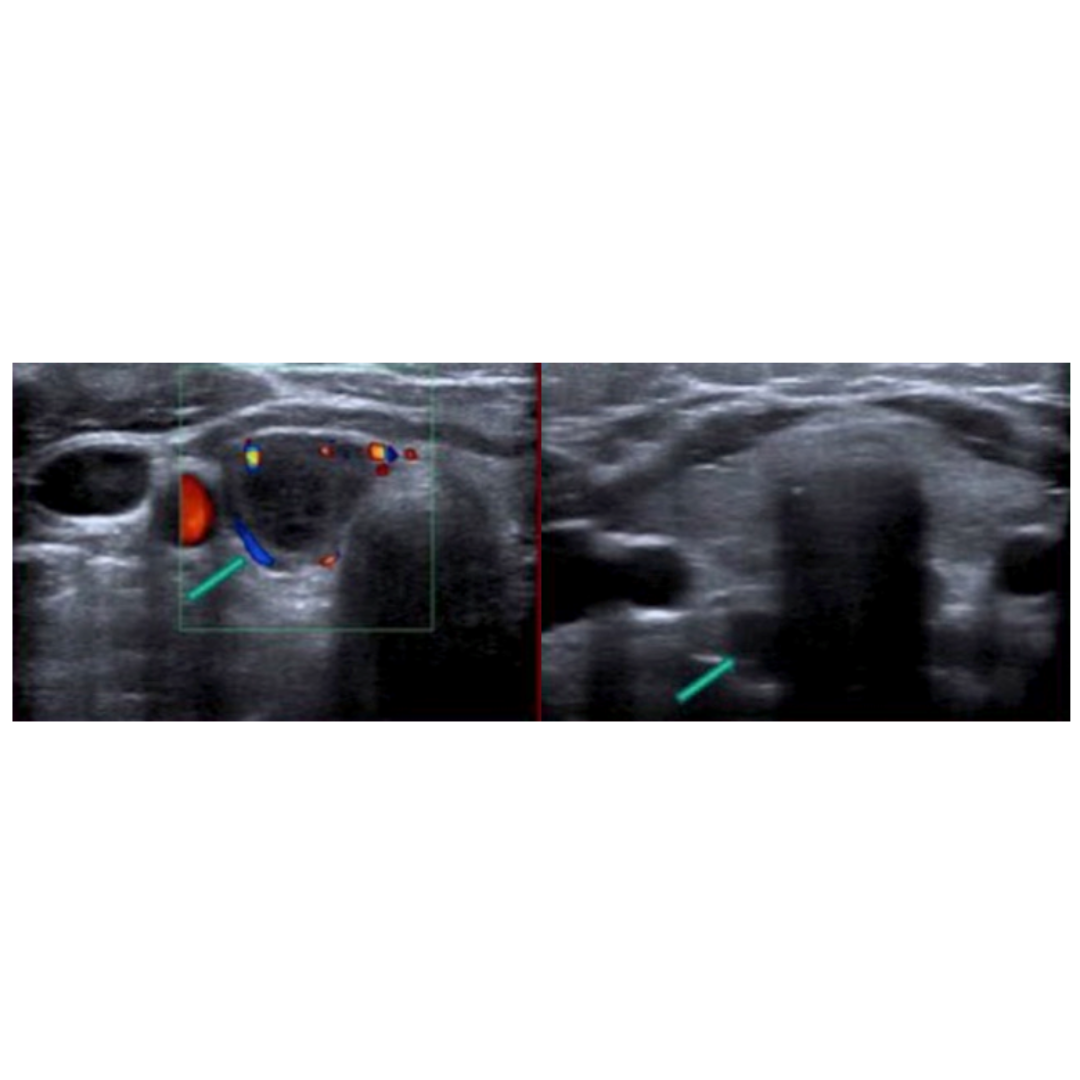

Figura 5: Ecografía de cuello que muestra lesión hipoecogénica profunda al polo inferior del lóbulo tiroideo derecho (flecha verde). La lesión corresponde a un nódulo heterogéneo solido-quístico, con flujo al Doppler en el componente sólido.